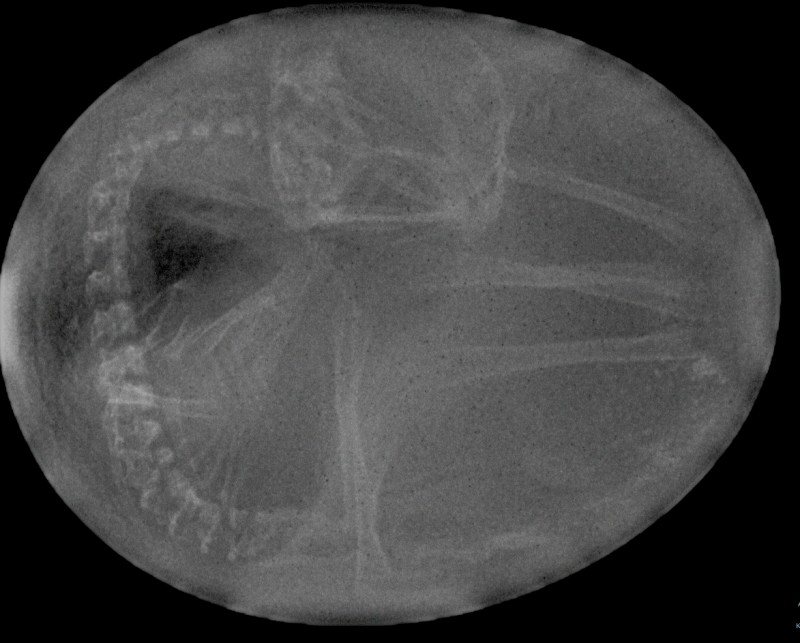

ja, vor allem haben 2 einen verlängerten Lidstrich und schwarze Flaumfedern auf dem Kopf. Fast wie Popper. Keine Ahnung, wo die herkommen. Im Rassestandard sind sie jedenfalls nicht .Hahn und Hennen waren unter ständiger Kontrolle. Es sind wahre Überraschungseier :DSputnik ist ein ganz helles Küken. Er entzieht sich meiner Kontrolle. Ich habe ihm zur Unterscheidung einen Kükenring ans Bein gemacht. Ganz harmlos, ganz locker, keine 2min später war er ab. Soviel dazu. Bis jetzt ist er noch der Kleinste. Nachdem aus dem 8. Ei kein Lebenszeichen kam, kein Wackler, kein Piepen, habe ich es mit zur Arbeit genommen und noch ein Bild gemacht. Aus blanker Neugierde und wenn man schon mal die Möglichkeit hat. Tja, es sollte nicht sein. Aber dafür hat es jetzt ein schönes Grab unter einer Halesia monticola.Chica, komm vorbei, das Kükenglück begießenHübsch sind die!